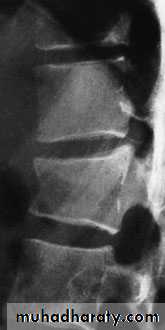

Axial compression or burst injury

Severe axial compression may ‘explode’ the vertebral body, causing failure of both the anterior and the middle columns. The posterior column is usually, but notalways, undamagedAnteroposterior x-rays may show

spreading of the vertebral body with an increase of the interpedicular distance

Posterior displacement of bone into the

spinal canal (retropulsion) is difficult to see on the plain lateral radiograph; a CT is essential.

If there is minimal anterior wedging and the fracture

is stable with no neurological damage, the patientis kept in bed until the acute symptoms settle (usually

under a week) and is then mobilized in a thoracolumbar brace or body cast which is worn for about 12 weeks.

However, any new symptoms such as tingling,

weakness or alteration of bladder or bowelfunction must be reported immediately and should

call for further imaging by MRI; anterior decompression

and stabilization may then be needed if there are

signs of present or impending neurological compromise